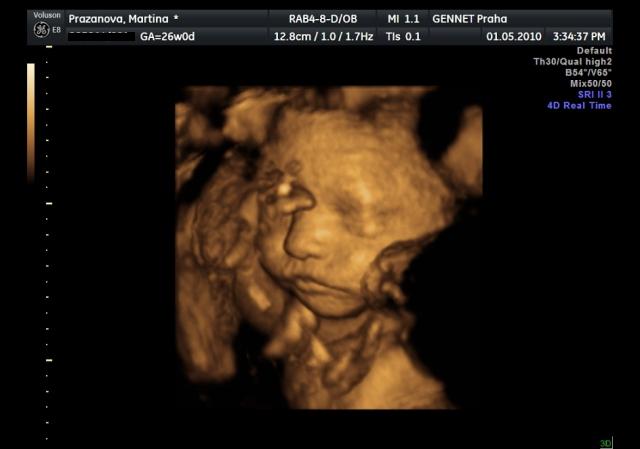

Už se nemůžeme dočkat 1.5....jdeme na 4D UTZ, tak doufám, že se nám ten náš klučík ukáže v plné své kráse 🙂))